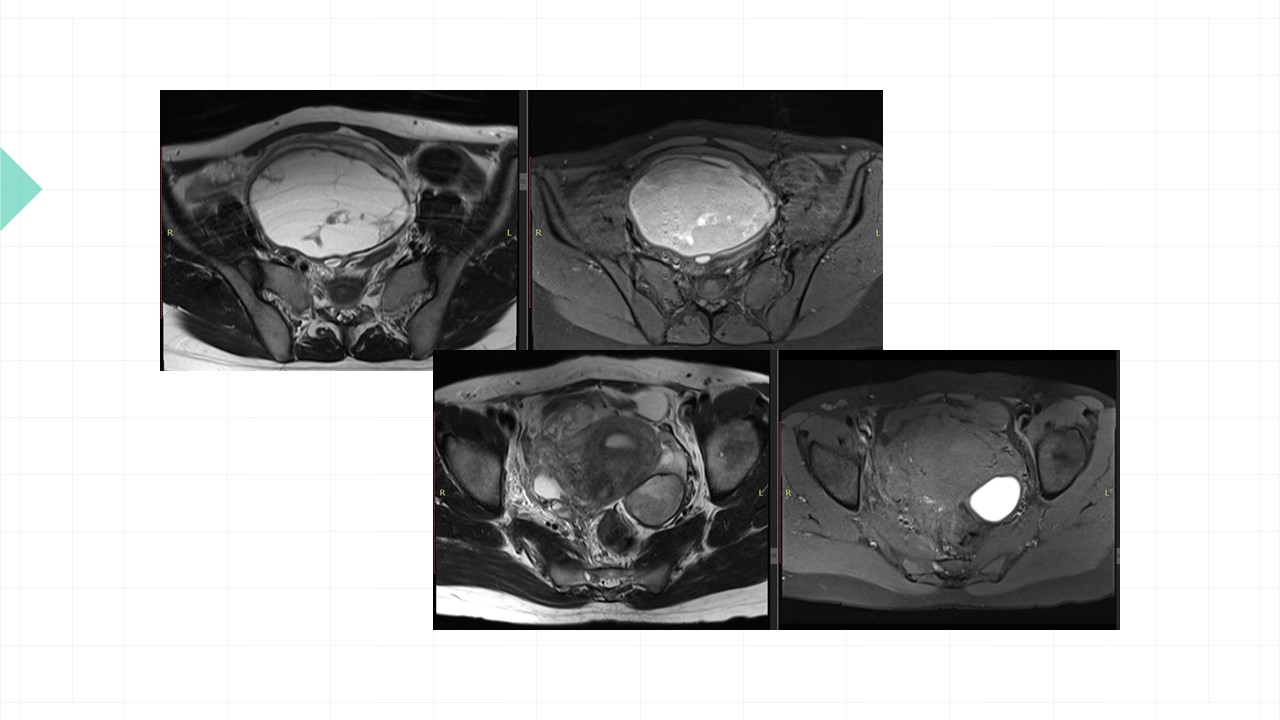

Vai trò cộng hưởng từ trong đánh giá lạc nội mạc tử cung

Từ khóa: Vai trò cộng hưởng từ trong đánh giá lạc nội mạc tử cung